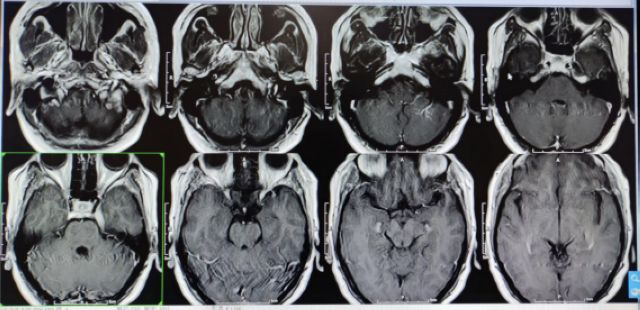

伽玛刀治疗前

伽玛刀治疗后

近期,徐女士来院复查

颅内肿瘤明显减小

治疗效果极佳